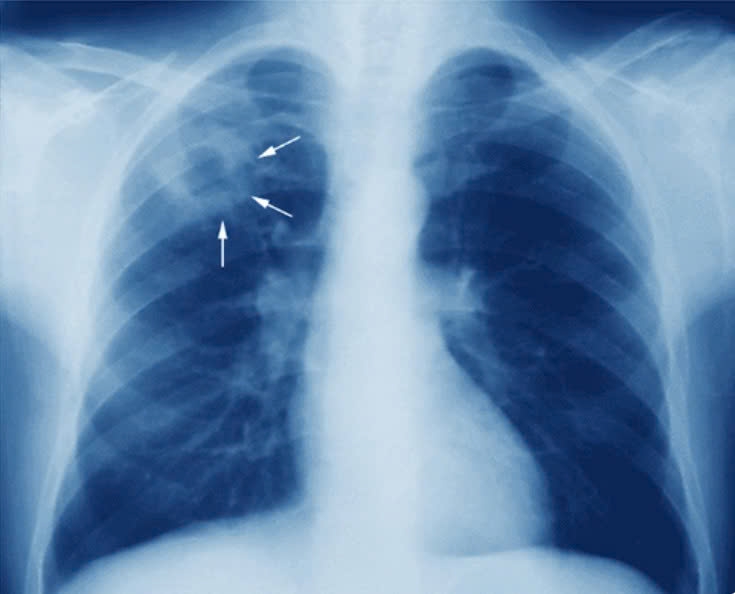

Việc kết hợp tầm soát lao trong các đợt khám sức khỏe định kỳ sẽ giúp người dân phát hiện bệnh ngay từ giai đoạn sớm, khi triệu chứng còn chưa rõ ràng.

Bằng tất cả tâm huyết vì sức khỏe và chất lượng cuộc sống của mỗi người dân, Trung tâm Y tế Thủy Nguyên với đội ngũ Thầy thuốc giàu kinh nghiệm, hệ thống khám, chữa bệnh Đa khoa có quy mô 500 giường bệnh kế hoạch, được trang bị máy chụp Cộng hường từ (MRI), máy chụp Cắt lớp vi tính (CT-Scanner) hiện đại, hệ thống X-Quang kỹ thuật số tiên tiến cùng hệ thống Xét nghiệm đồng bộ chắc chắn là ĐIỂM TỰA CHO SỨC KHỎE Cộng đồng nói chung, trong công tác phòng, chống bệnh lao nói riêng.